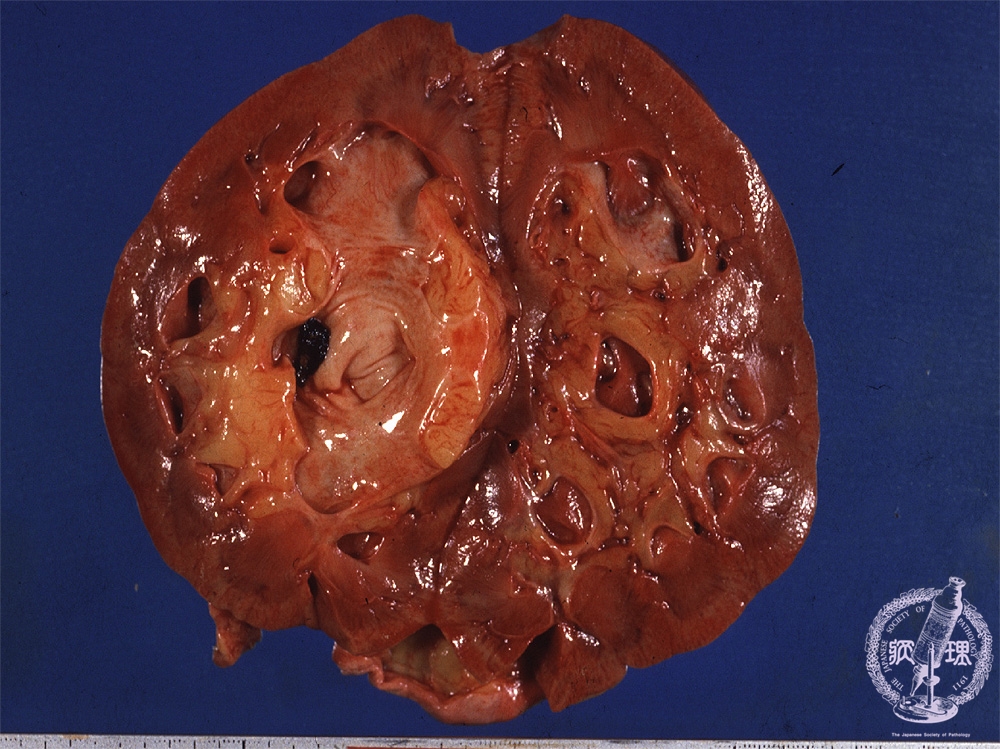

- (14)Nephrolithiasis

Gross findings: The renal pelvis contains a black-colored concretion (yellow arrow). This case also presents hydronephrosis. Note the dilated pelvis (yellow dotted line).